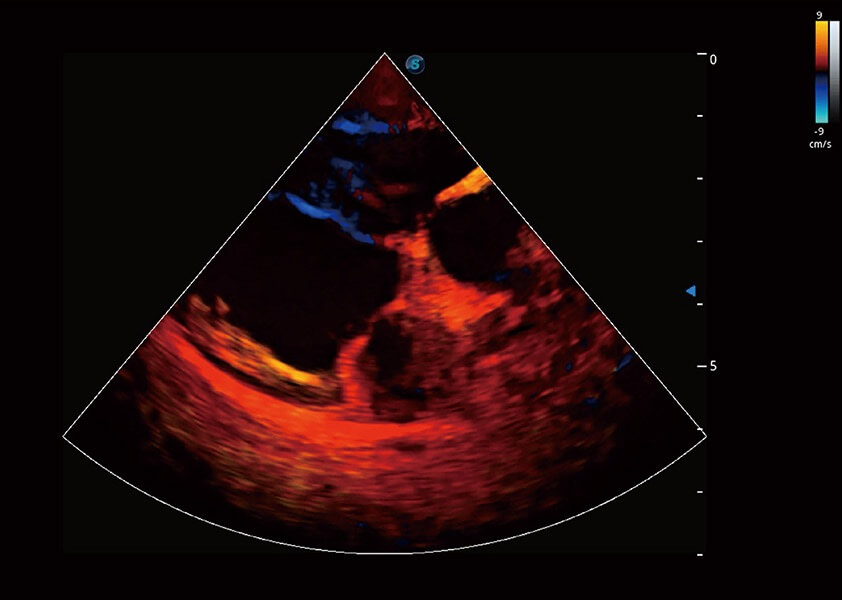

ProPet 60 作为一款高端台式动物超声设备,为动物医生的日常诊断提供了一系列贴合动物临床需求、解决临床实际问题的高级成像功能。凭借全系列高清探头,满足医生对腹部、心脏、生殖、浅表、肌骨等成像的所有需求,切实帮助您提升检查效率,提高诊断信心。

动物是人类最亲密的朋友和最值得信赖的伙伴。银河优越会也一直致力于探索动物专用的超声影像解决方案。 全新推出的ProPet系列,是银河优越会在动物超声影像智能化、专业化、精准化的一次跨越式革新。动物不能用言语来表述自己的不适,通过超声影像,ProPet系列搭建了动物医生与不同物种沟通的“桥梁”,为动物医生注入了“治愈之力”。